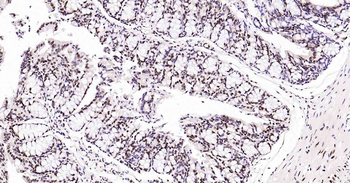

100 μl, 200 μl, 50 μl - LATS2 Rabbit Polyclonal Antibody [orb6306]Featured

IF, IHC-Fr, IHC-P, WB

Human, Mouse, Rat

Bovine, Canine, Equine, Gallus, Rabbit

Rabbit

Polyclonal

Unconjugated

100 μl, 200 μl, 50 μl - Featured